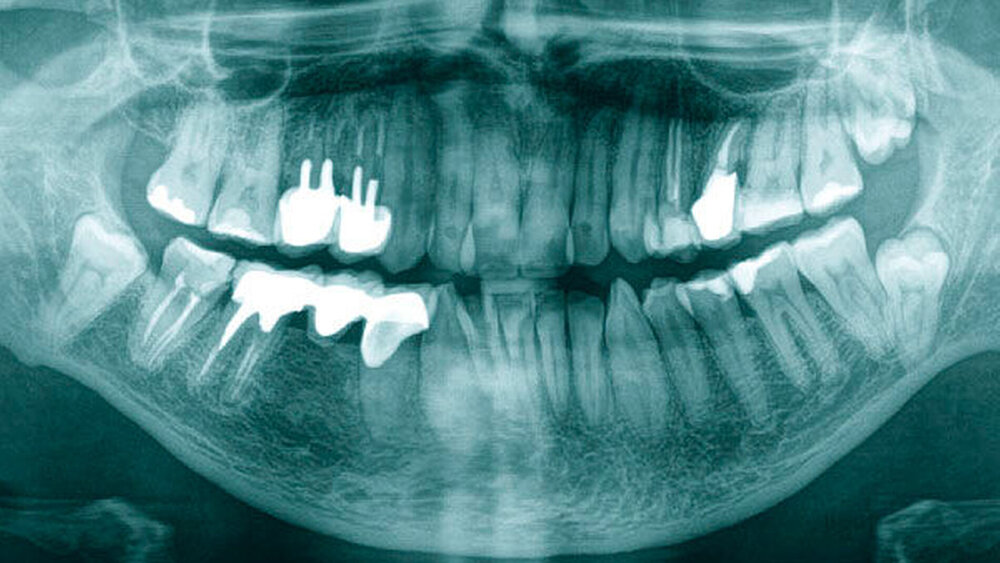

Die vom Kollegen angefertigte Panoramaschichtaufnahme (Abbildung 1) zeigte neben multiplen wurzelgefüllten Zähnen einen in Infraposition befindlichen Zahn 28, einen retinierten Zahn 38 sowie einen retinierten Zahn 48. Da die Zahnwurzeln beider Unterkiefer-Weisheitszähne sehr nah an den Unterkieferrand und in unmittelbarer Nähe zum Mandibularkanal projiziert wurden, entschieden wir uns, eine digitale Volumentomografie (DVT) anzufertigen, um die Lagebeziehung zum Nervus alveolaris inferior weiter abzuklären und die Operation planen zu können.